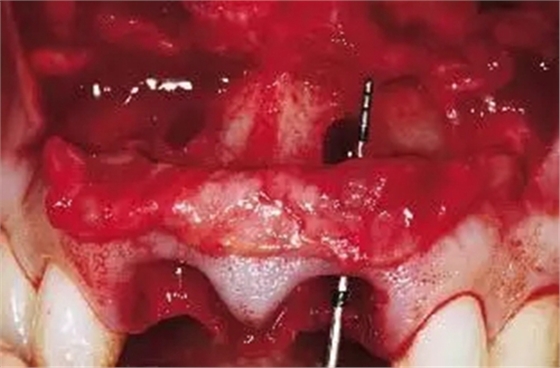

圖2、翻開全厚瓣可見明顯的牙根縱裂,唇側(cè)骨板2/3受到累及而缺損。